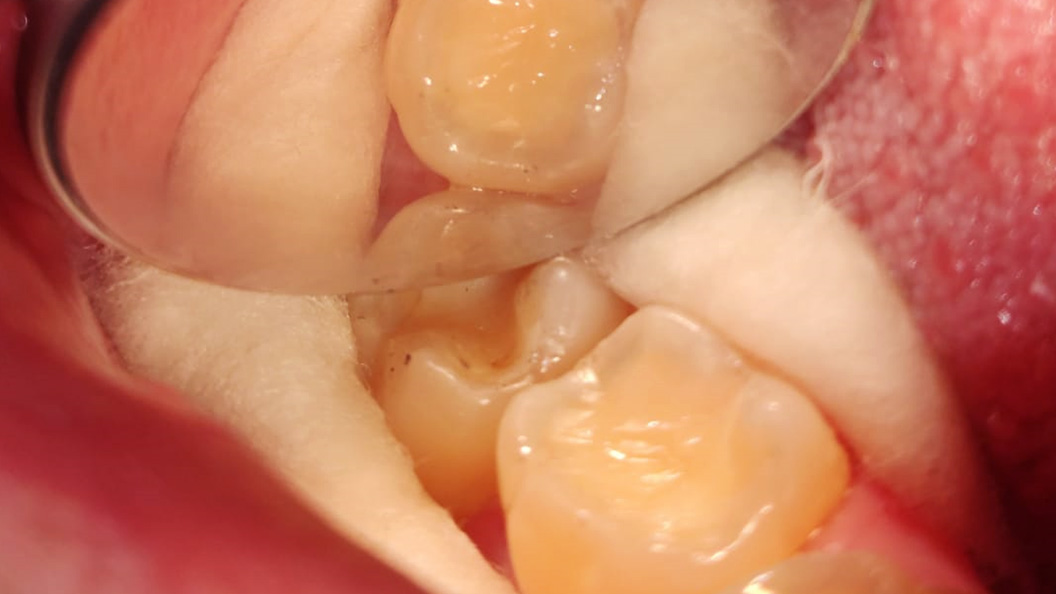

До и после лечения

Пациент обратился в клинику с жалобами на эстетику в области нижнего жевательного зуба справа. Отмечена небольшая чувствительность при приёме холодной пищи. После обработки полости под контролем кариес маркера, был выявлен глубокий кариес, дно и стенки полости плотные, пульпа не затронута. Наш специалист Григорьев Пётр Игоревич поставил диагноз: хронический глубокий кариес 3.6 зуба. После этого был составлен и утверждён план лечения.

В ходе лечения были проведены следующие работы:

- с использование системы коффердам проведена механическая обработка полости

- медикаментозная обработка с использованием хлоргексидина 2%

- поставлена пломба Fuji II A3

- проведена проверка окклюзионных контактов, шлифовка и полировка